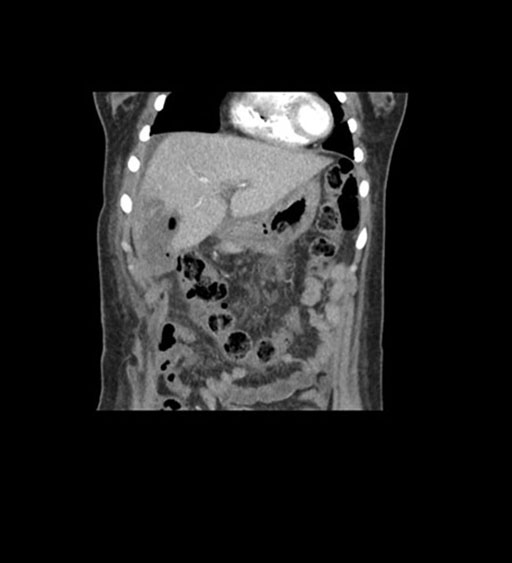

Coronal Arterial

Coronal Venous